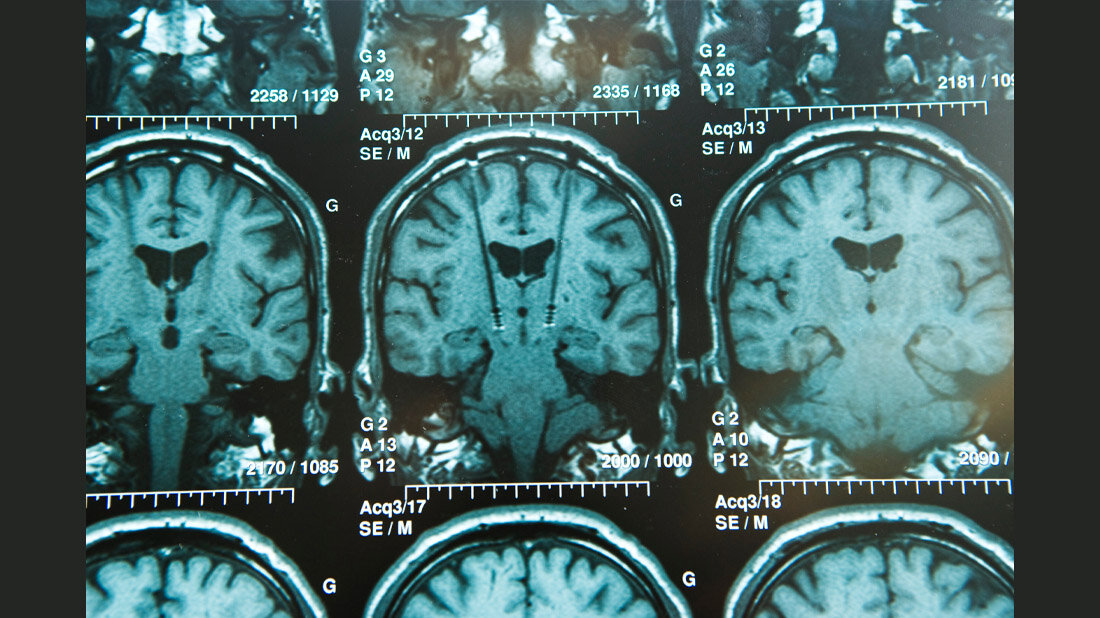

Mit weltweit mehr als 100 Millionen Untersuchungen pro Jahr ist die Magnetresonanztomografie (MRT) das zweitwichtigste medizinische Bildgebungsverfahren nach dem Röntgen. Ein neuer Ansatz könnte Millionen von Patientinnen und Patienten mit Implantaten helfen und die Arbeit des Radiologiepersonals erheblich vereinfachen. Denn wer ein Implantat trägt, muss oftmals auf diese potenziell lebensrettende Diagnosemöglichkeit verzichten oder eine geringere Bildqualität in Kauf nehmen. Insbesondere aktive Implantate wie Herzschrittmacher und Neurostimulatoren können in Kombination mit einer MR-Untersuchung bei unvorsichtiger Anwendung zu gefährlichen Erwärmungen im Körper führen. In der Physikalisch-Technischen Bundesanstalt (PTB) wurde nun demonstriert, wie mit einer drahtlosen Kommunikation zwischen Implantat und Magnetresonanztomograf dieses Problem gelöst werden kann.

Metallische Implantate im Körper stellen bei der Magnetresonanztomografie (MRT) ein Sicherheitsrisiko dar, da die Wechselwirkung des leitfähigen Implantats mit den starken elektromagnetischen Feldern des Tomografen zu einer gefährlichen Gewebeerwärmung führen kann. Das Personal muss im Einzelfall aufwendig und in eigener Verantwortung abwägen, ob ein MRT für die Gesundheit der Patientinnen oder Patienten vertretbar ist oder wie hoch die Strahlungsleistung ohne Gesundheitsschäden sein darf. „Wir wollen, dass ein ‚smartes‘ Implantat direkt mit dem MR-Scanner kommuniziert, der dann seinerseits die elektromagnetische Welle an das Implantat anpasst“, erklärt Dr. Lukas Winter, Wissenschaftler in der PTB. „So vermeiden wir eine Überhitzung und sorgen gleichzeitig für die bestmögliche Bildqualität. Für das Krankenhauspersonal wäre die Arbeitserleichterung enorm.“ Voraussetzung für die weitere Verbreitung dieser innovativen Technologie ist eine enge Zusammenarbeit von Implantat- und MRT-Herstellerfirmen – unterstützt von geeigneten Normen und Standards.